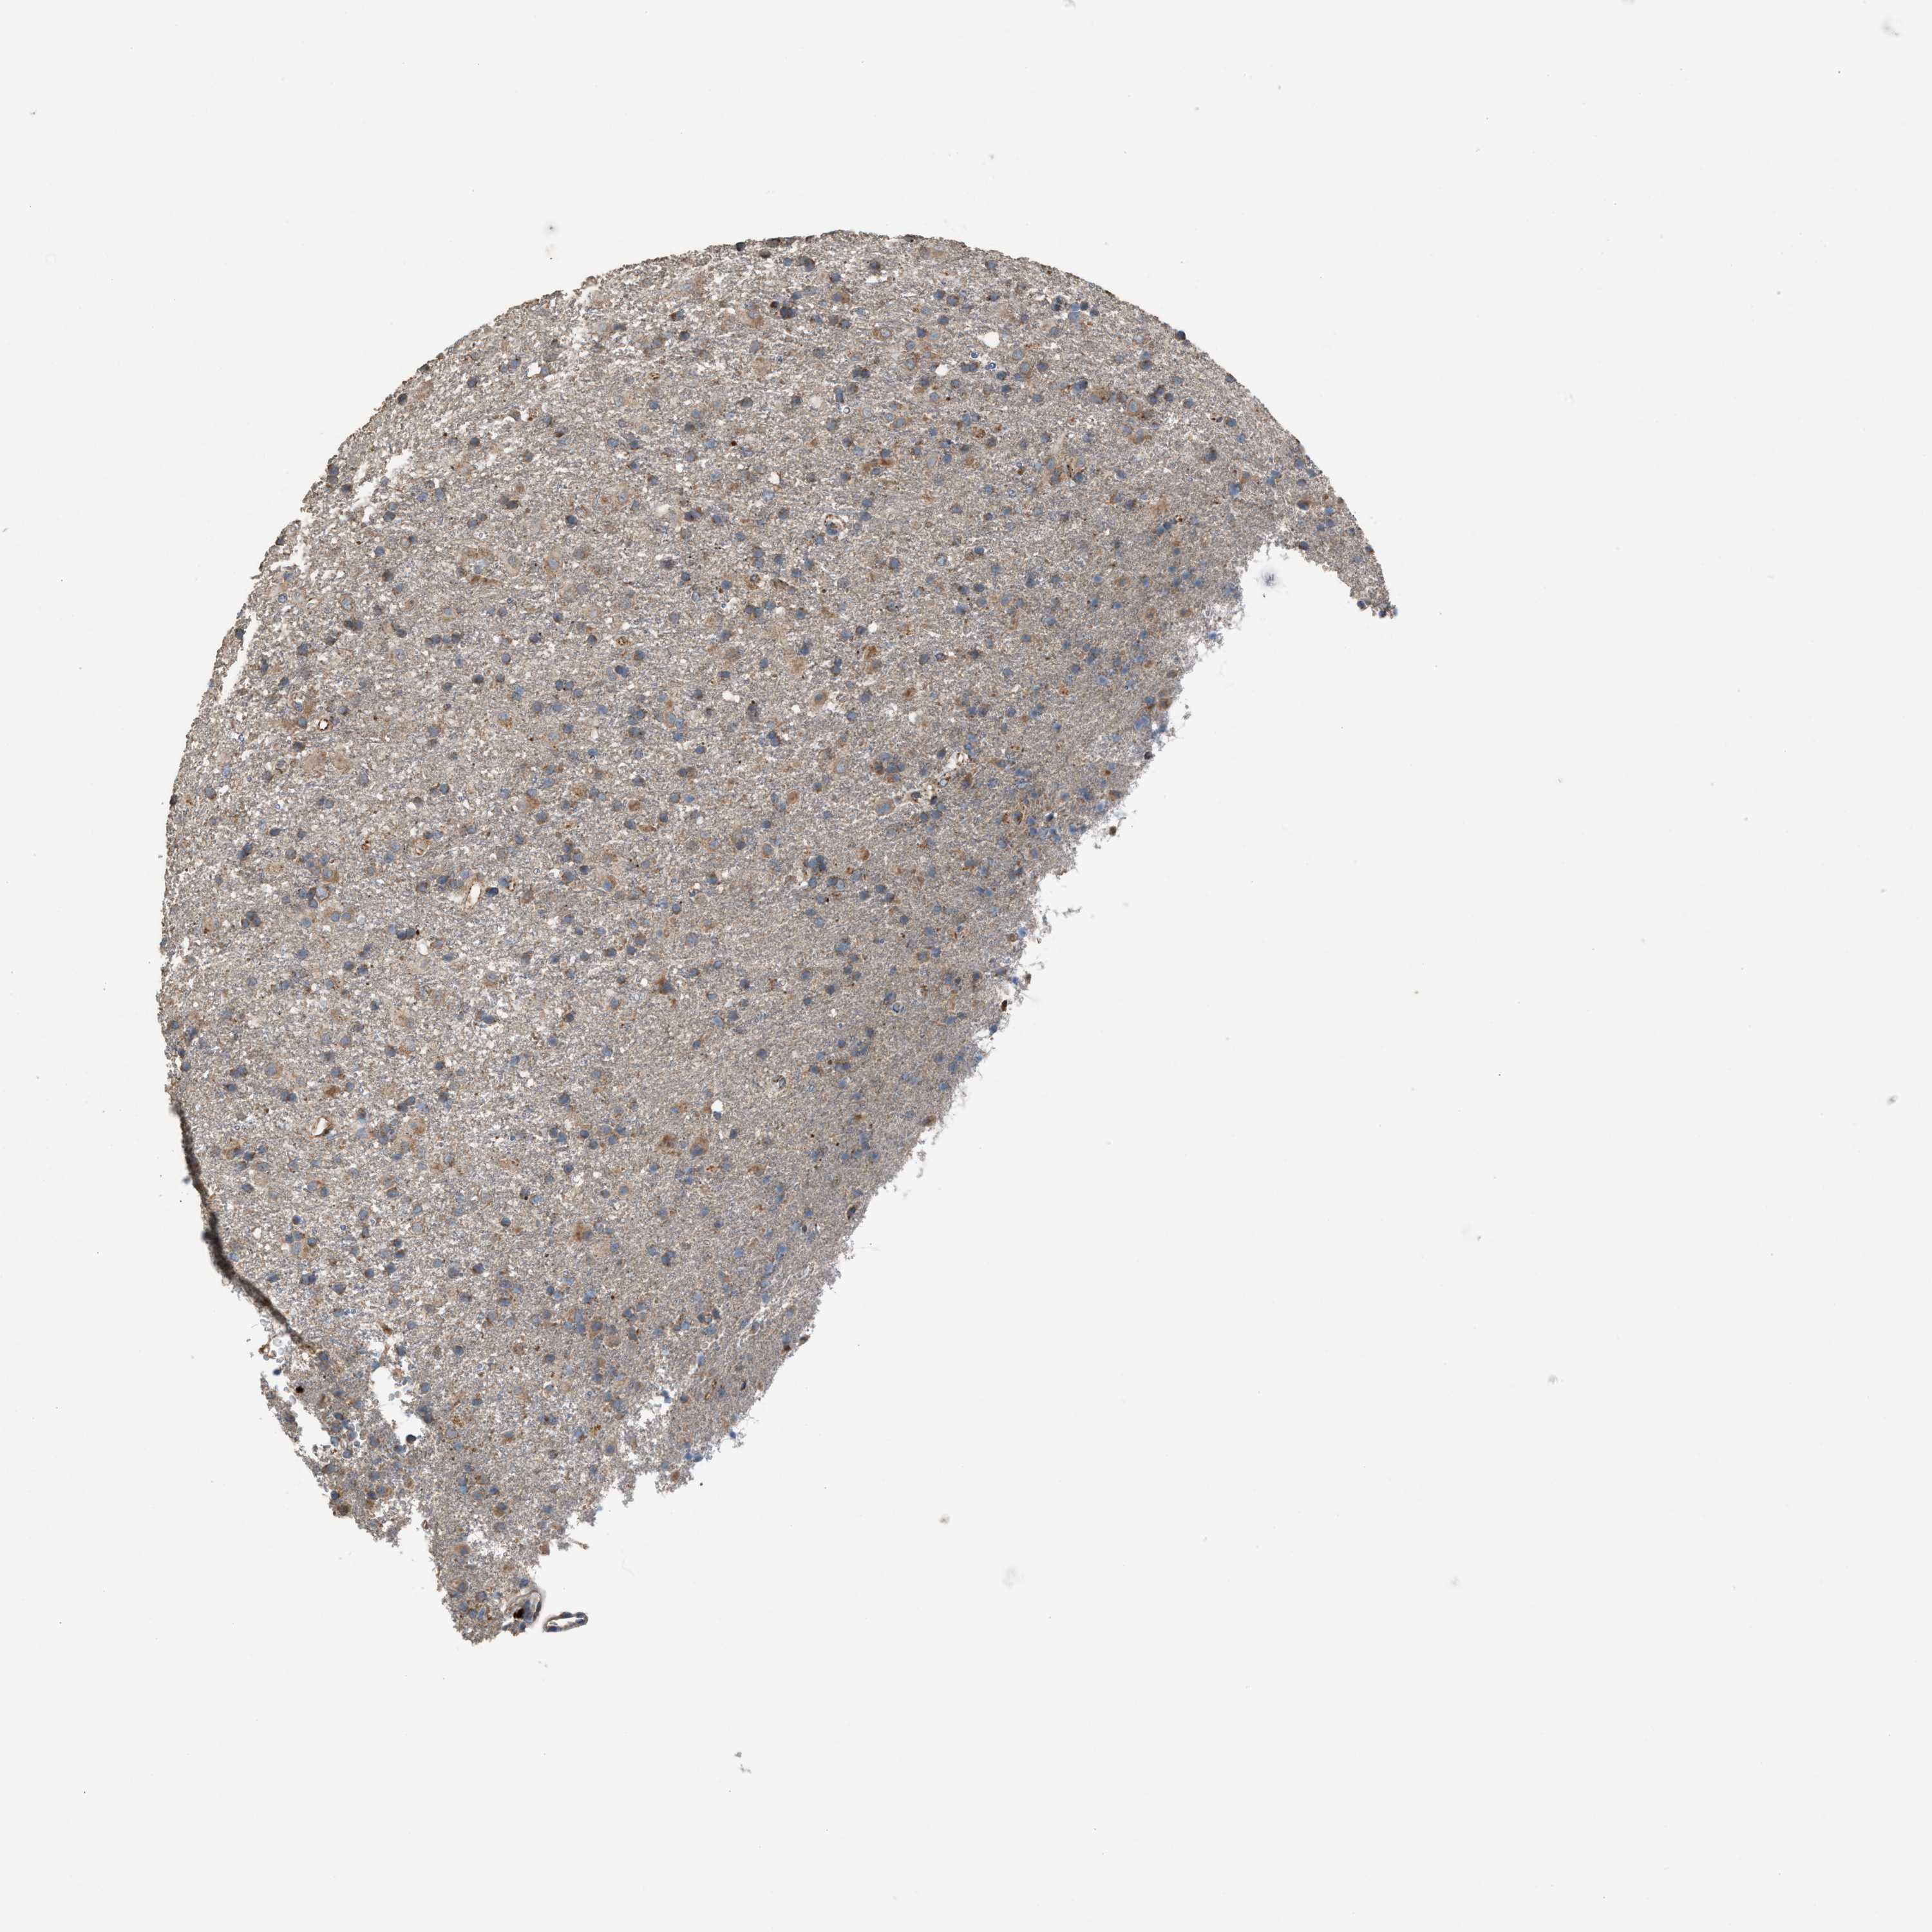

GLIOMA - Protein expressioni

A mouse-over function shows sample information and annotation data. Click on an image to view it in a full screen mode. Samples can be filtered based on level of antibody staining by selecting one or several of the following categories: high, medium, low and not detected. The assay and annotation is described here.

Note that samples used for immunohistochemistry by the Human Protein Atlas do not correspond to samples in the TCGA dataset.

Antibody stainingi

Antibody staining in the annotated cell types in the current human tissue is reported as not detected, low, medium, or high, based on conventional immunohistochemistry profiling in selected tissues. This score is based on the combination of the staining intensity and fraction of stained cells.

Each image is clickable and will lead to virtual microscopy that enables deeper exploration of all samples and also displays staining intensity scores, fraction scores and subcellular localization as well as patient and tissue information for each sample.

Antibody HPA021545

Antibody HPA021849

Staining

High

Medium

Low

Not detected

Intensity

Strong

Moderate

Weak

Negative

Quantity

>75%

75%-25%

<25%

None

Location

Nuclear

Cytoplasmic/membranous

Cytoplasmic/membranous,nuclear

Glioma, malignant, High grade

Glioma, malignant, Low grade